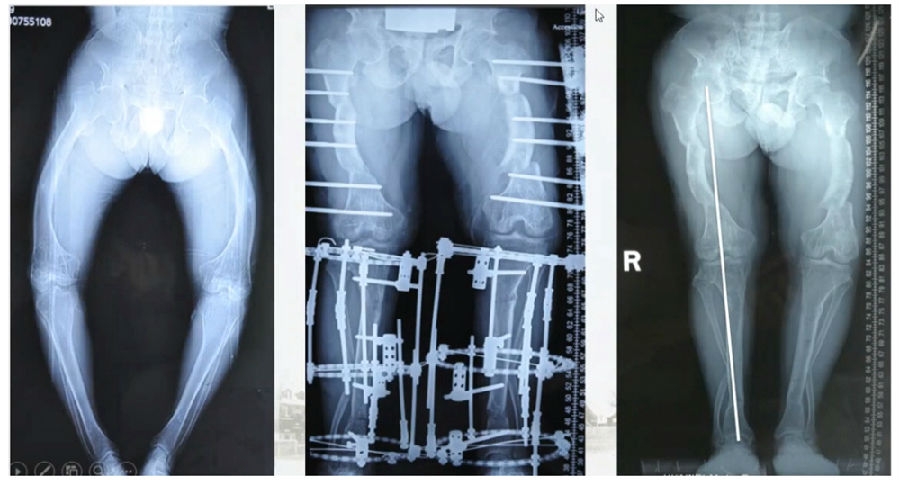

典型病例,女性,35岁,农民,左膝内翻、短缩、内旋。

术前

泰勒外固定架缓慢矫正短缩、内翻、前弓、内旋。

术中

该患者截骨后,做MAD矫正,目标MAD=0。患者术后1个月即达到设计的效果。

术后1个月

典型病例2,男性,52岁,双膝疼痛,低磷佝偻病,复合畸形。

股骨畸形即时矫正,胫骨畸形缓慢矫正。

手术前后对比

手术前后外观